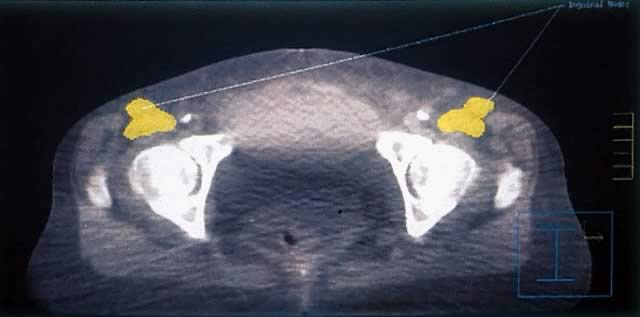

Treatment planning CT scans as shown in Figure 5 can localize superficial and deep inguinal nodes that can be readily identified at the level of inguinofemoral vessels. At the time of simulation, fiducial markings correspond to the central rays of the radiation beam and are visible on the subsequent CT scan facilitating digital reconstruction of dose distribution in axial, coronal, and sagittal planes. Figure 6 shows a composite dose distribution in the axial plane of the mixed photon and electron fields of Figures 3 and 4. Each of the dose regions (or isodose curves) represented by the various lines is normalized to a reference at the central axis. The delivered dose is close to 100% of the prescribed dose across the entire region corresponding to the marked groin nodes on the planning CT from Figure 5. Optimization of dose delivery with treatment planning software and improved imaging should permit individualized radiation therapy. In-field failures potentially can be significantly reduced with careful attention to treatment technique and patients' individual anatomic considerations.

Fig. 5. Computed tomography planning. Inguinal nodes are outlined and variable in depth below overlying skin.

Fig. 6. Anteroposterior/posteroanterior dosimetry plan for groin and pelvis.